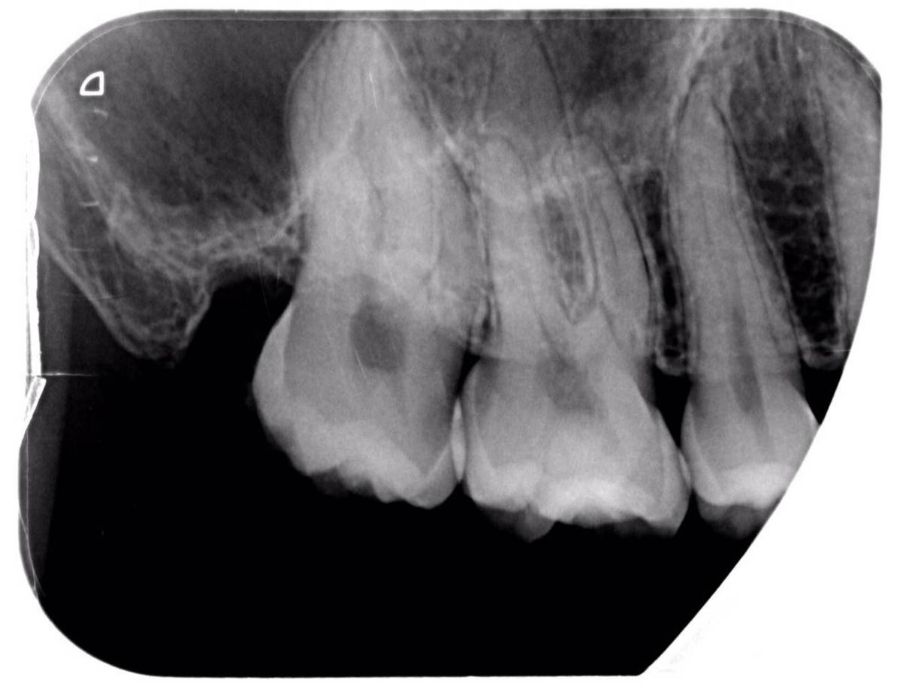

术前X光片

根1.jpg

全口口腔卫生状况可。17近中邻、颌面龋达牙本质深层,可探及穿髓孔、探痛,有持续性血红色渗出液,无叩痛,冷、热诊持续痛,牙龈无明显红肿,BOP(—),PD2~3mm,无松动。松动(-)。15、16间邻、颌面中龋,冷热诊一过性敏感,无叩痛。45缺失,余牙未见明显异常。x-ray示:17近中邻、颌面低密度影近髓,mb根管大角度S弯且中段根管影像模糊,高密度影怀疑为钙化物影像,根尖未见明显低密度影。

MB根管走向分析

根2.jpg